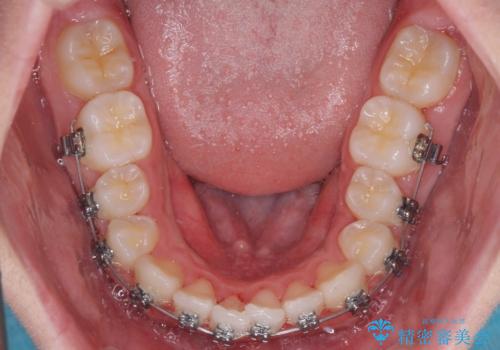

- メタルブラケット

- 11ヶ月

- 10-30回

中学生であることから、治療期間を短縮できると判断し、ワイヤー矯正にて短期間で治療を行うこととしました。

叢生のため磨き残しの多い歯列でしたが、1年弱で治療を終了でき、磨き残しや歯肉の腫れが著しく改善されました。